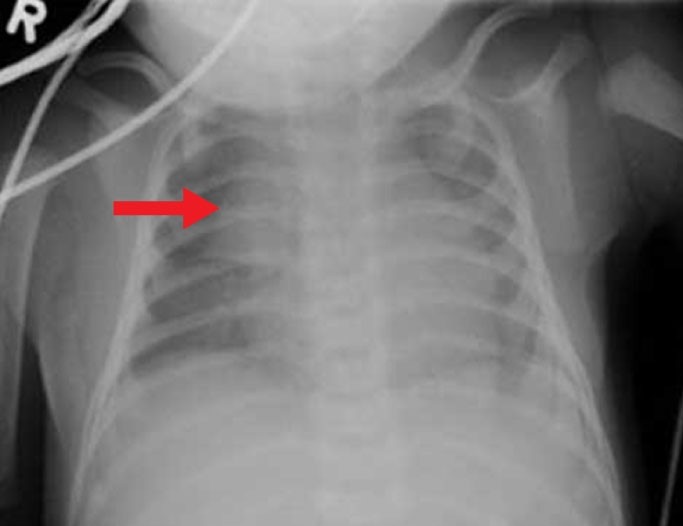

A 5-month-old full-term boy is brought to the physician for fever.  He was doing well until this morning, when he felt warm to his mother.  He has had a "runny nose" and intermittent coughing but otherwise has been breastfeeding well.  His 3-year-old brother had an upper respiratory tract infection last week.  The infant takes vitamin D, and his vaccinations are up to date.  His temperature is 38. 9 C (102 F) , blood pressure is 90/60 mm Hg, pulse is 120/min, and respirations are 32/min.  Pulse oximetry shows an oxygen saturation of 96%.  Examination shows crusted rhinorrhea at the nares.  The patient's chest radiograph is shown below. A 5-month-old full-term boy is brought to the physician for fever.  He was doing well until this morning, when he felt warm to his mother.  He has had a  runny nose  and intermittent coughing but otherwise has been breastfeeding well.  His 3-year-old brother had an upper respiratory tract infection last week.  The infant takes vitamin D, and his vaccinations are up to date.  His temperature is 38. 9 C (102 F) , blood pressure is 90/60 mm Hg, pulse is 120/min, and respirations are 32/min.  Pulse oximetry shows an oxygen saturation of 96%.  Examination shows crusted rhinorrhea at the nares.  The patient's chest radiograph is shown below.   Which of the following is marked on this patient's chest radiograph? A) Hilar lymphadenopathy B) Right atrium C) Right middle-lobe infiltrate D) Right upper-lobe atelectasis E) Right upper-lobe infiltrate F) Thymus Which of the following is marked on this patient's chest radiograph?

A) Hilar lymphadenopathy

B) Right atrium

C) Right middle-lobe infiltrate

D) Right upper-lobe atelectasis

E) Right upper-lobe infiltrate

F) Thymus